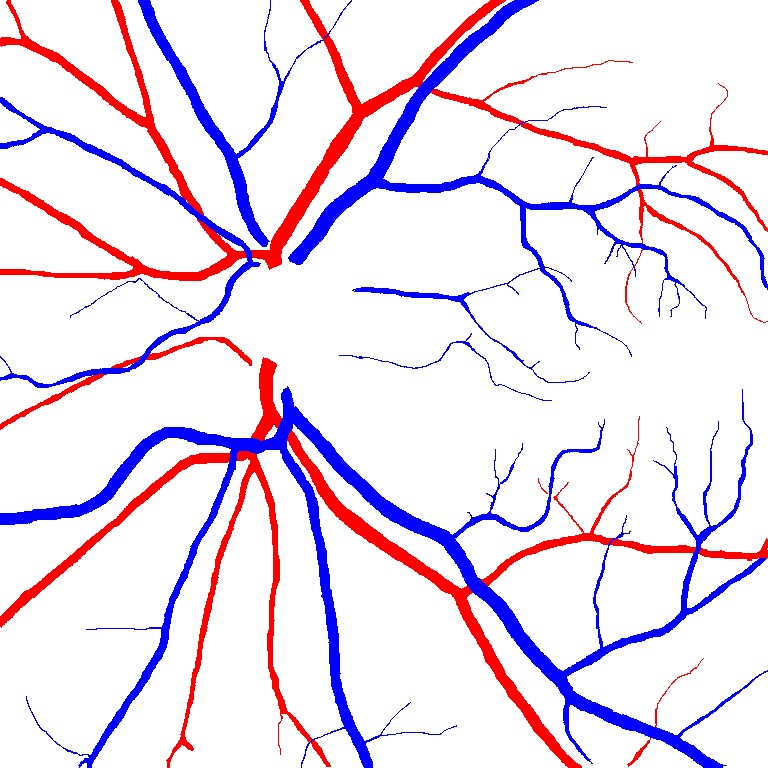

Table V presents quantitative performance benchmarks of SegRAVIR and other competing approaches for retinal artery and vein classification on the RITE dataset [11]. SegRAVIR outperforms previous state-of-the-art approaches in terms of accuracy, sensitivity, and specificity. Fig. 5 provides a qualitative comparison between segmentation outputs of SegRAVIR and the method of Hemelings et al. [40] on the RITE test set.

(a) (b) (c)

(a) (b) (c)